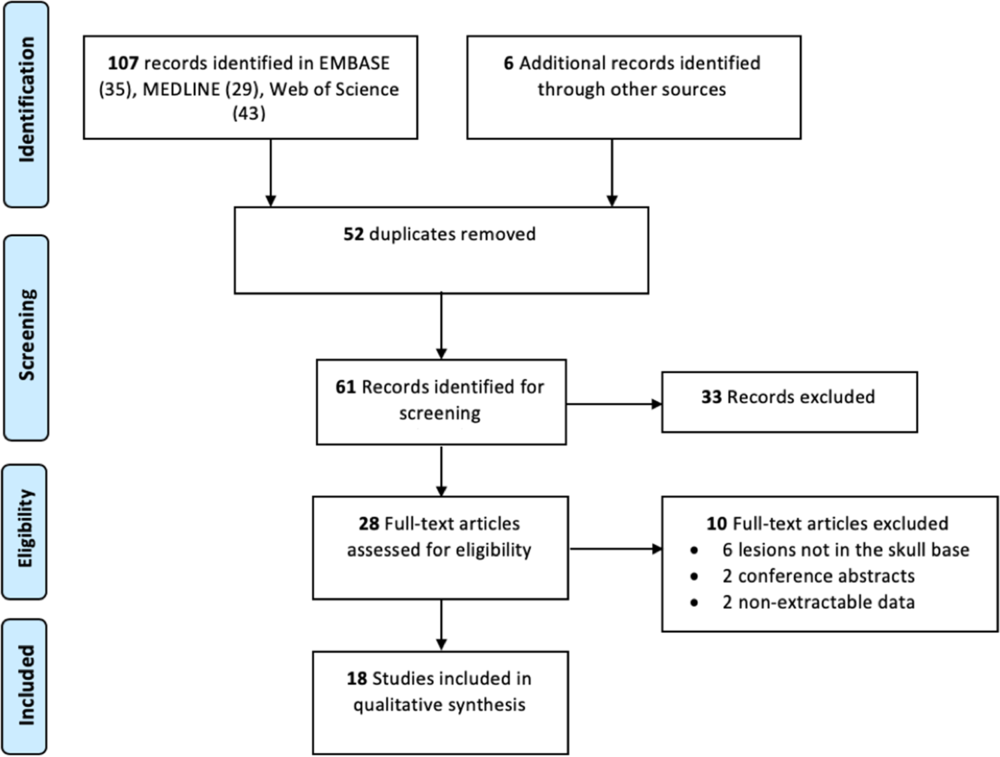

A systematic review of the literature was conducted on skull base CAPNONs. MEDLINE, EMBASE, and the Cochrane Central Register of Controlled Trials (CENTRAL) were searched from the inception of the database until June 2019. This systematic review is reported in accordance with the Preferred Reporting Items in Systematic Reviews and Meta-Analyses. Search terms included keyword such as “CAPNON” and combinations of the following words: “calcified,” “pseudo-neoplasm,” “pseudoneoplasm,” “pseudo-tumor,” “pseudotumor,” “neuro-axis,” and “neuraxis.” Screening of searched titles, abstracts, and full texts was done independently by two reviewers, and any discrepancies that occurred during the title and abstract screening stages were resolved by automatic inclusion to ensure that all relevant publications were not missed.

Our literature search identified 113 potentially relevant records. After abstract and full-text screening, 18 records were identified including 23 unique cases of skull base CAPNONs (Figure 5, Table 1).Reference Alshareef, Vargas, Welsh and Kalhorn4,Reference Garen, Powers, King and Perot7–Reference Kocovski, Parasu, Provias and Popovic11,Reference Bertoni, Unni, Dahlin, Beabout and Onofrio13–Reference Wisniewski, Janczar, Tybor, Papierz and Jaskolski24 All 24 patients (including our previously unpublished case) were symptomatic, with 11 (45.8%) patients presenting with cranial neuropathies (Table 1).Reference Garen, Powers, King and Perot7–Reference Nonaka, Aliabadi, Friedman, Odere and Fukushima9,Reference Bertoni, Unni, Dahlin, Beabout and Onofrio13,Reference Hodges, Karikari and Nimjee16,Reference Nussbaum, Hilton and Defillo20 One patient (Case 5) was managed conservatively,Reference Bertoni, Unni, Dahlin, Beabout and Onofrio13 and one patient (Case 22) underwent a biopsy of the lesion,Reference Blood, Rodriguez, Nolan, Ramanathan and Desai14 while the rest underwent resection of the lesion. Analysis of patients with documented extents of resection revealed that 10 patients underwent gross total resection and 6 underwent subtotal resection of CAPNONs. Among all 24 patients, only 2 patients (Cases 1 and 23) had complete resolution of the symptoms postoperatively,Reference Garen, Powers, King and Perot7,Reference Peker, Aydin and Baskaya22 while most patients remained stable.

Figure 5: Preferred Reporting Items in Systematic Reviews and Meta-Analyses flow diagram outlining the search strategy results from initial search to included studies.